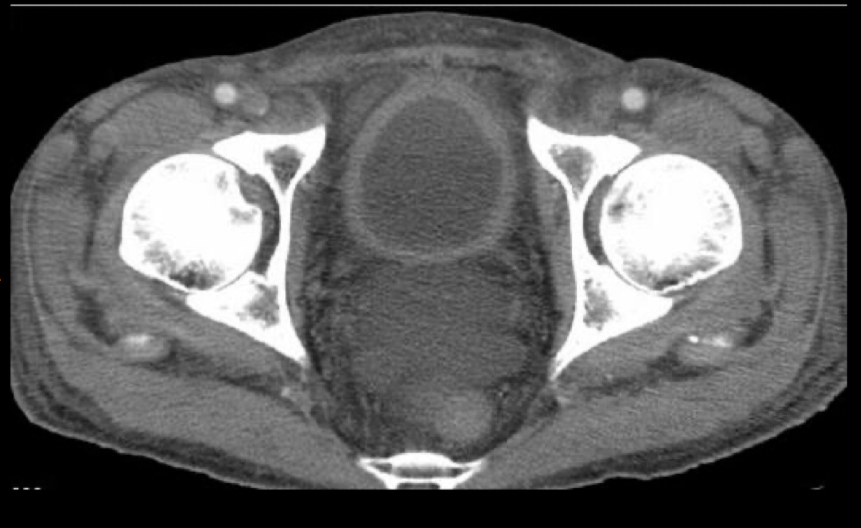

Que se ve en tc de la cistitis

A

• paredes engrosadas

• Burbujas en pared: cistitis enfisematosa: DM2. Xq bacterias anaerobias llenas de gas

• Capta contraste